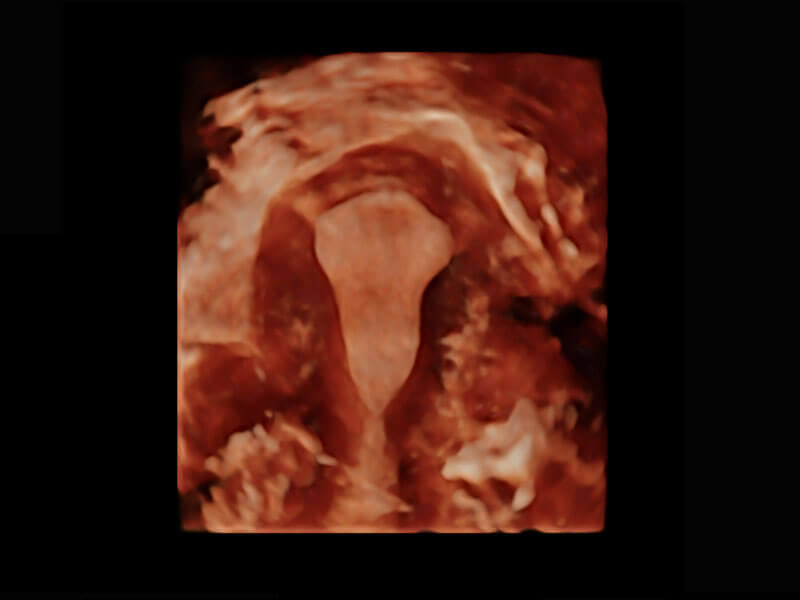

• 腔内三维-宫内节育器

• 腔内妇科-宫腔分离

• 腔内妇科-卵巢

• 腔内三维-光影成像